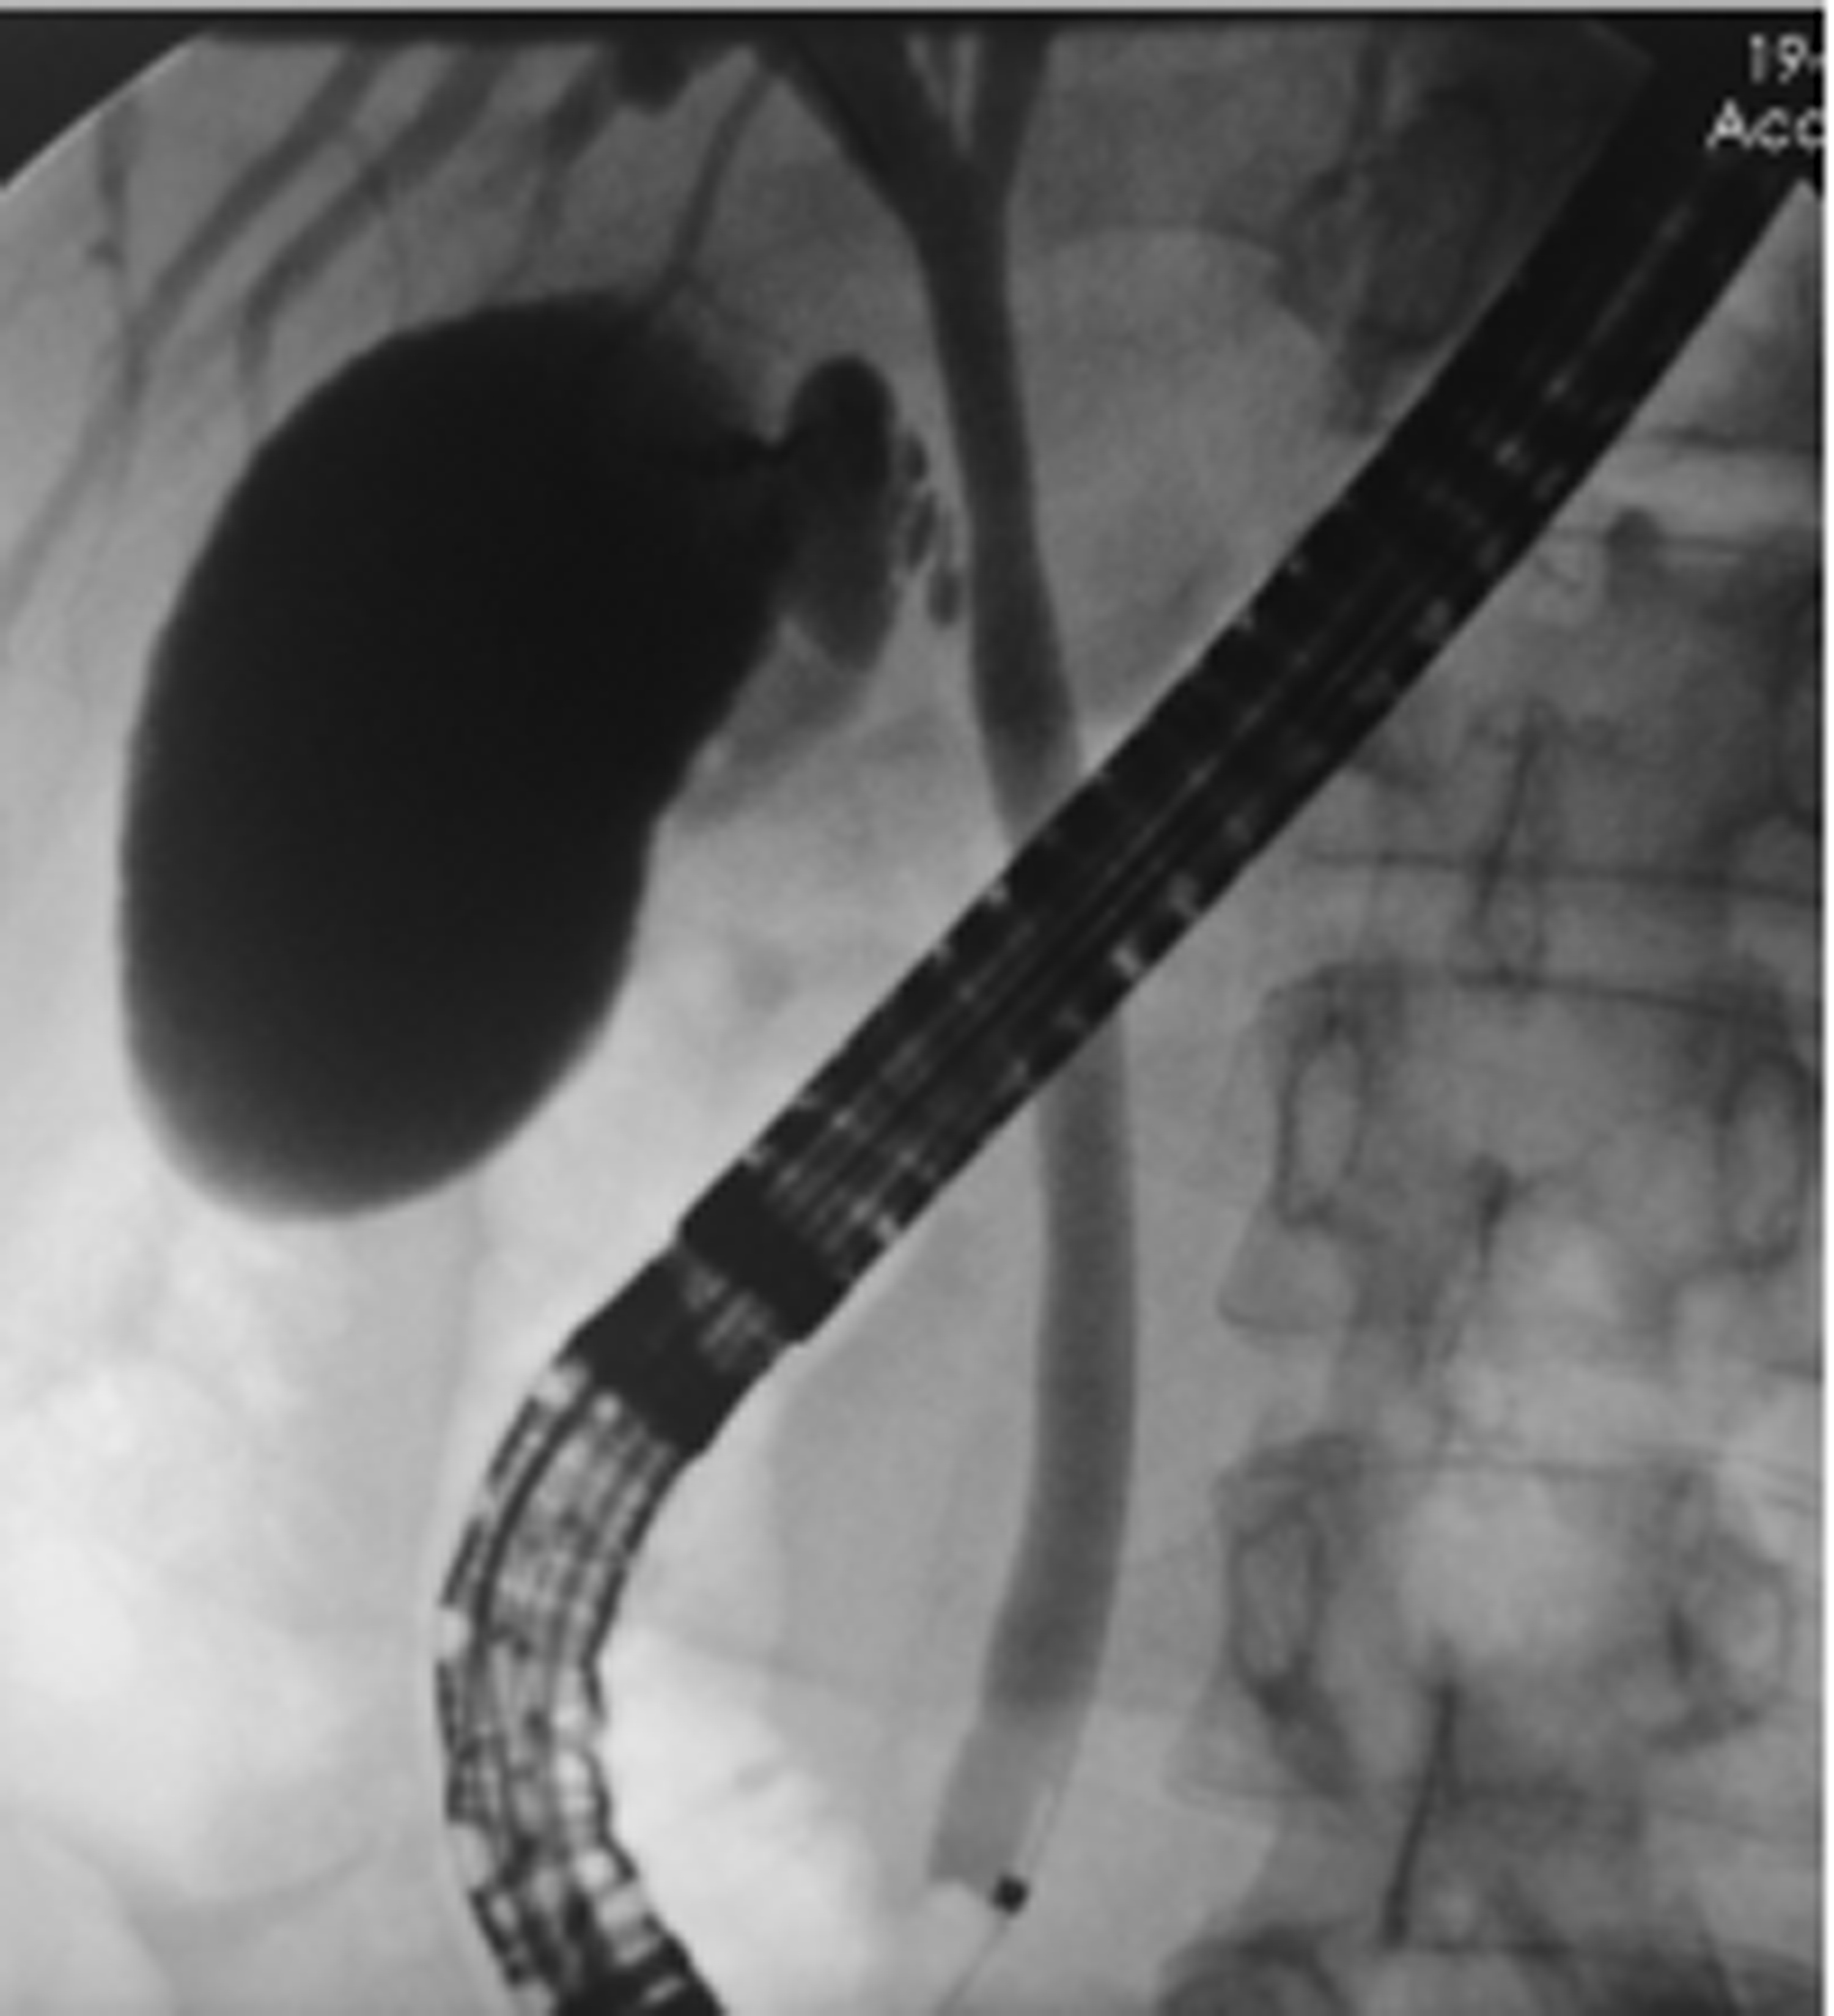

Selection of treatment regimens for pancreatic duct stones: A comparative analysis

Abstract:

Objective  To investigate the clinical efficacy of endoscopic retrograde cholangiopancreatography (ERCP), laparoscopy, and laparotomy in the treatment of pancreatic duct stones (PDS) by collecting related clinical data, to summarize the experience in selecting treatment regimens for PDS, and to further explore feasible treatment regimens that could maximize and optimize the benefits of PDS patients.  Methods  A retrospective analysis was performed for the clinical data of 131 PDS patients who were treated in Gongli Hospital Affiliated to Naval Medical University from June 2014 to December 2018, and according to the surgical procedure, they were divided into ERCP group with 69 patients, laparoscopy group with 32 patients, and laparotomy group with 30 patients. Related indices were monitored before and after treatment, and surgical outcome was compared between the laparoscopy group and the laparotomy group. The independent samples t-test was used for comparison of normally distributed continuous data between two groups; a one-way analysis of variance was used for comparison between multiple groups, and the least significant difference t-test or the SNK-q test was used for further comparison between two groups. The Mann-Whitney U test was used for comparison of continuous data with skewed distribution between two groups, and the Kruskal-Wallis H test was used for comparison between multiple groups. An repeated measures analysis of variance and the Friedman test were used for comparison of related indices before and after surgery, and the chi-square test was used for comparison of categorical data between groups.  Results  Among the 131 PDS patients, there were 40 patients with type Ⅰ PDS, 76 with type Ⅱ PDS, and 15 with type Ⅲ PDS. There was no significant difference in the distribution of main surgical methods between the laparoscopy group and the laparotomy group (χ2=1.93, P > 0.05). There were significant differences between the laparoscopy group and the laparotomy group in the dynamic changes of white blood cell count, C-reactive protein, procalcitonin, and Homeostasis Model Assessment of Insulin Resistance after surgery (F=24.68, χ2=227.66, F=45.37, F=106.71, all P < 0.05). Compared with the laparotomy group, the laparoscopy group had significantly shorter time of operation, significantly lower intraoperative blood loss, significantly shorter time to first flatus after surgery, a significantly lower frequency of use of pain-relieving drugs, shorter time to extraction of abdominal drainage tube, lower incidence rates of short-term postoperative complications, and a significantly shorter length of postoperative hospital stay (t=-4.80, t=-9.43, Z=-6.78, t=-11.59, Z=-6.77, χ2=9.24, t=-3.60, all P < 0.05). The incidence rate of short-term postoperative complications was 24.64% in the ERCP group, 28.13% in the laparoscopy group, and 66.67% in the laparotomy group, with a significant difference between groups (χ2=17.12, P < 0.05), and the ERCP group and the laparoscopy group had a significantly lower incidence rate of short-term postoperative complications than the laparotomy group (χ2=15.78 and 9.24, P < 0.05 and P=0.02). The treatment response rate was 91.30% in the ERCP group, 93.75% in the laparoscopy group, and 73.33% in the laparotomy group, with a significant difference between the three groups (χ2=7.70, P=0.02), and the ERCP group and the laparoscopy group had a significantly better response rate than the laparotomy group (χ2=5.56 and 4.77, P=0.02 and 0.03).  Conclusion  ERCP is the preferred method for minimally invasive treatment of some patients with type Ⅰ/Ⅱ PDS and is safe and effective with few serious complications. Surgical operation is an important method for the treatment of complex PDS, but with complicated techniques and difficult operation. Compared with laparotomy, laparoscopy has the advantages of small trauma, few serious complications, and high abdominal pain remission rate and can significantly shorten the time of operation, reduce intraoperative blood loss, and shorten the length of postoperative hospital stay. Therefore, laparoscopy should be the preferred regimen for the treatment of complex PDS.